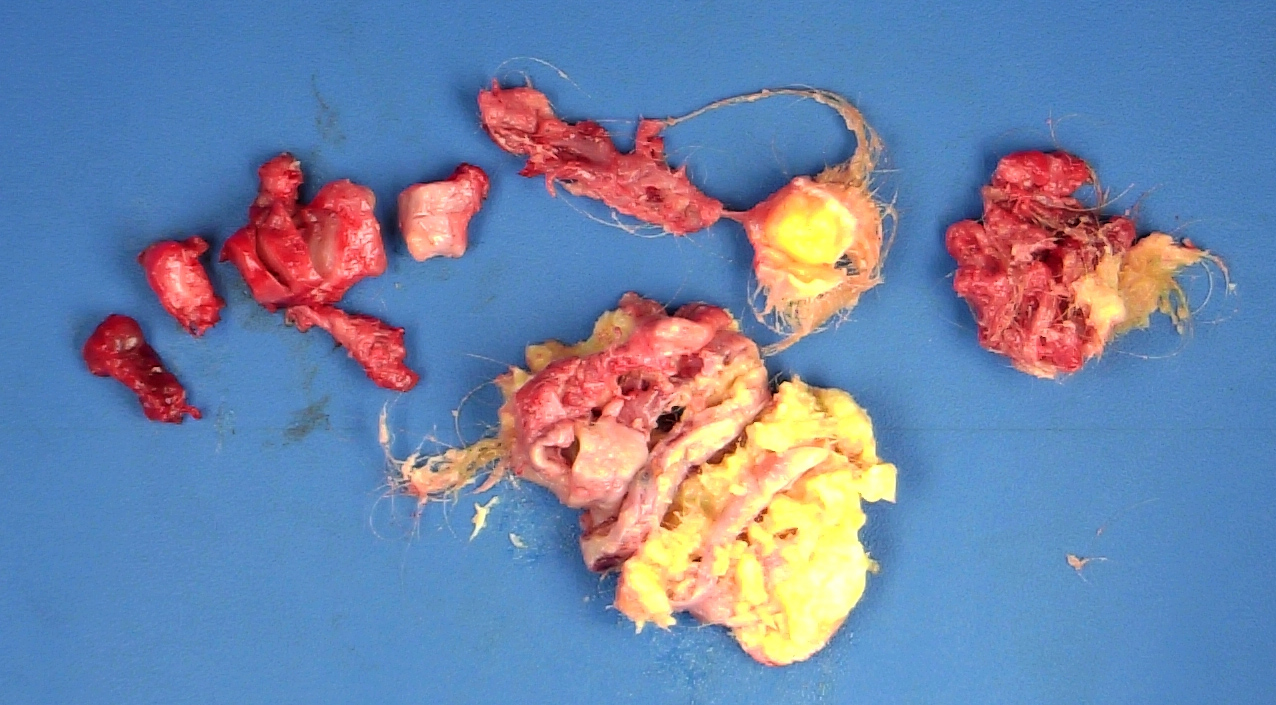

Gross description

- Smooth cyst that may contain hair, teeth, cartilage, bone or sebaceous material

- Generally < 10 cm

- Raised protuberance in cyst wall (Rokitansky nodule)

- Reference: StatPearls: Cystic Teratoma [Accessed 29 July 2021]

Gross images

D. Mature teratoma. The photo shows a mass with yellow sebaceous material and hair. In a 19 year old woman, this most likely represents a mature teratoma. Mature teratomas are the most common ovarian tumor and are especially common in women of reproductive age.